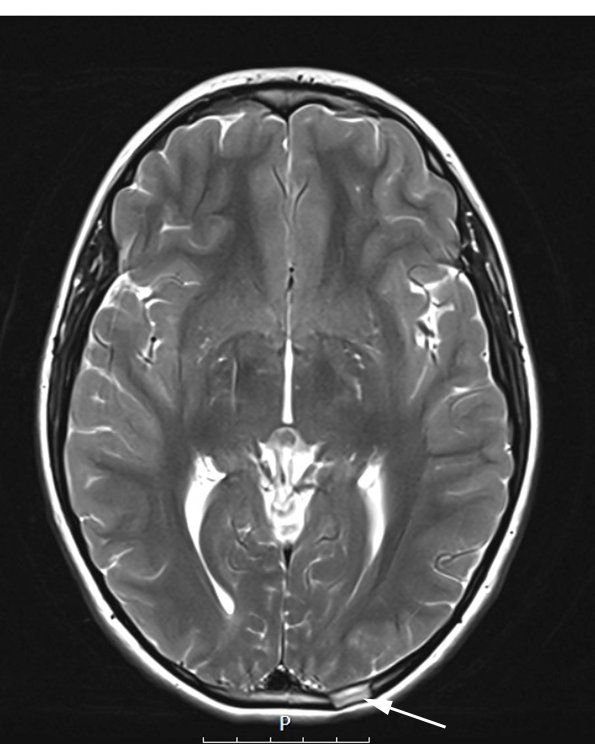

Case 24 History (Thanks S Dahiya) ---- The patient is a 13-year-old boy with a traumatic skull injury 11 years previously. About 2 months prior to his current admission, he noted a bump on his scalp which has been somewhat painful to touch. On imaging, he was found to have a T2 hyperintense left parietal calvarial lesion. Operative procedure: Left occipital skull mass resection. ---- 24A1,2 These T2-weighted scans demonstrate a focus of hyperintensity in the left parietal calvarial region (arrow, 24A1, no contrast) and a T2 dark fluid (24A2) scan without contrast.